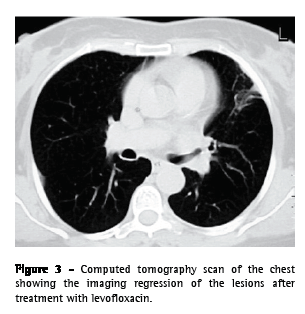

A 55-year-old Caucasian female, a secretary and a nonsmoker, sought treatment in the emergency room. The patient had a history of chronic hepatitis B, arterial hypertension, mixed dyslipidemia, and multiple untreated dental caries. She reported a three-week history of daily diarrhea, heartburn, retrosternal discomfort that was aggravated in the supine position, asthenia, anorexia, and weight loss (5 kg). One week after the onset of symptoms, the patient presented progressively worsening chest pain (on the left side) with pleuritic characteristics, frequent fits of dry cough upon exertion, and an isolated peak of fever had appeared. The electrocardiogram results were normal, and endoscopy of the upper digestive tract revealed a compliant cardia and antral gastritis. A chest X-ray showed a heterogeneous hypotransparency, with loss of substance in its center, in the middle third of the left lung field. A computed tomography scan of the chest revealed a 4-cm mass with heterogeneous content and pleural extension to the level of the lingula, as well as two micronodules in the posterior region of the right lung field (Figure 1). An etiological study was carried out based on the working diagnosis of pulmonary neoplasia.

From the analytical study, we highlight the following results: an erythrocyte sedimentation rate of 98 mm in the first hour; a cancer antigen 125 level of 63.3 U.mL-1 (<35.0); a carcinoembryonic antigen level of 3.55 ng.mL-1 (<2.5); and a slight increase in the C-reactive protein level. The serum immunological study, the viral marker analysis, and the final analytical study revealed no other significant alterations. The results of colonoscopy, transabdominal pelvic ultrasound, mammography, and cervicovaginal cytology were normal. The first fiberoptic bronchoscopy performed showed diffused signs of inflammation at the level of the lingula. The cytological examinations of aspirate, bronchial lavage, and bronchoalveolar lavage were negative for neoplastic cells. Microbiological analysis under anaerobic conditions also yielded negative results, as did testing for acid-fast bacilli. The patient was then submitted to transthoracic needle aspiration biopsy (TNAB), which, in the extemporaneous cytological examination, showed an inflammatory process with suppuration. In view of this provisional result, antibiotic therapy with oral levofloxacin 500 mg daily was initiated, and it was decided that a second fiberoptic bronchoscopy should be carried out. However, the cytological examination of the TNAB revealed morphological aspects consistent with the presence of Actinomyces, confirmed through microbiological culture analysis of the bronchial and bronchoalveolar lavage of the second fiberoptic bronchoscopy, in which A. naeslundii was identified (Figure 2). Testing for acid-fast bacilli yielded negative results. Due to the clinical and radiological improvement after a month of treatment (Figure 3), we opted to maintain the antibiotic therapy already initiated, altering the dose schedule: intravenous levofloxacin (500 mg/day) for four weeks and oral levofloxacin (500 mg/day) thereafter. There were no adverse drug effects, and the treatment was continued for 16 weeks, until there was complete radiological normalization. Analytically, we observed a decrease in the erythrocyte sedimentation rate and in the initially altered levels of both tumor markers, as well as normalization of the C-reactive protein level. The patient was also submitted to dental treatment.